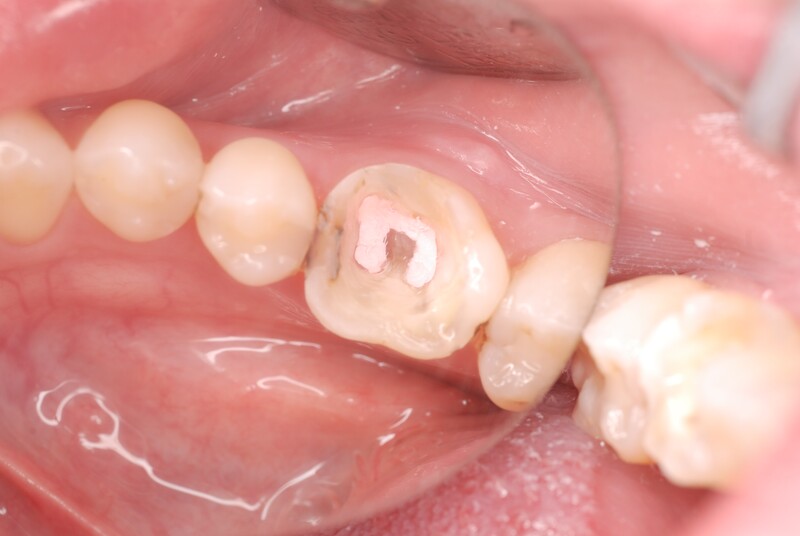

被せ物を外すと歯の神経である歯髄は死んでしまっており、歯に亀裂も認められます。